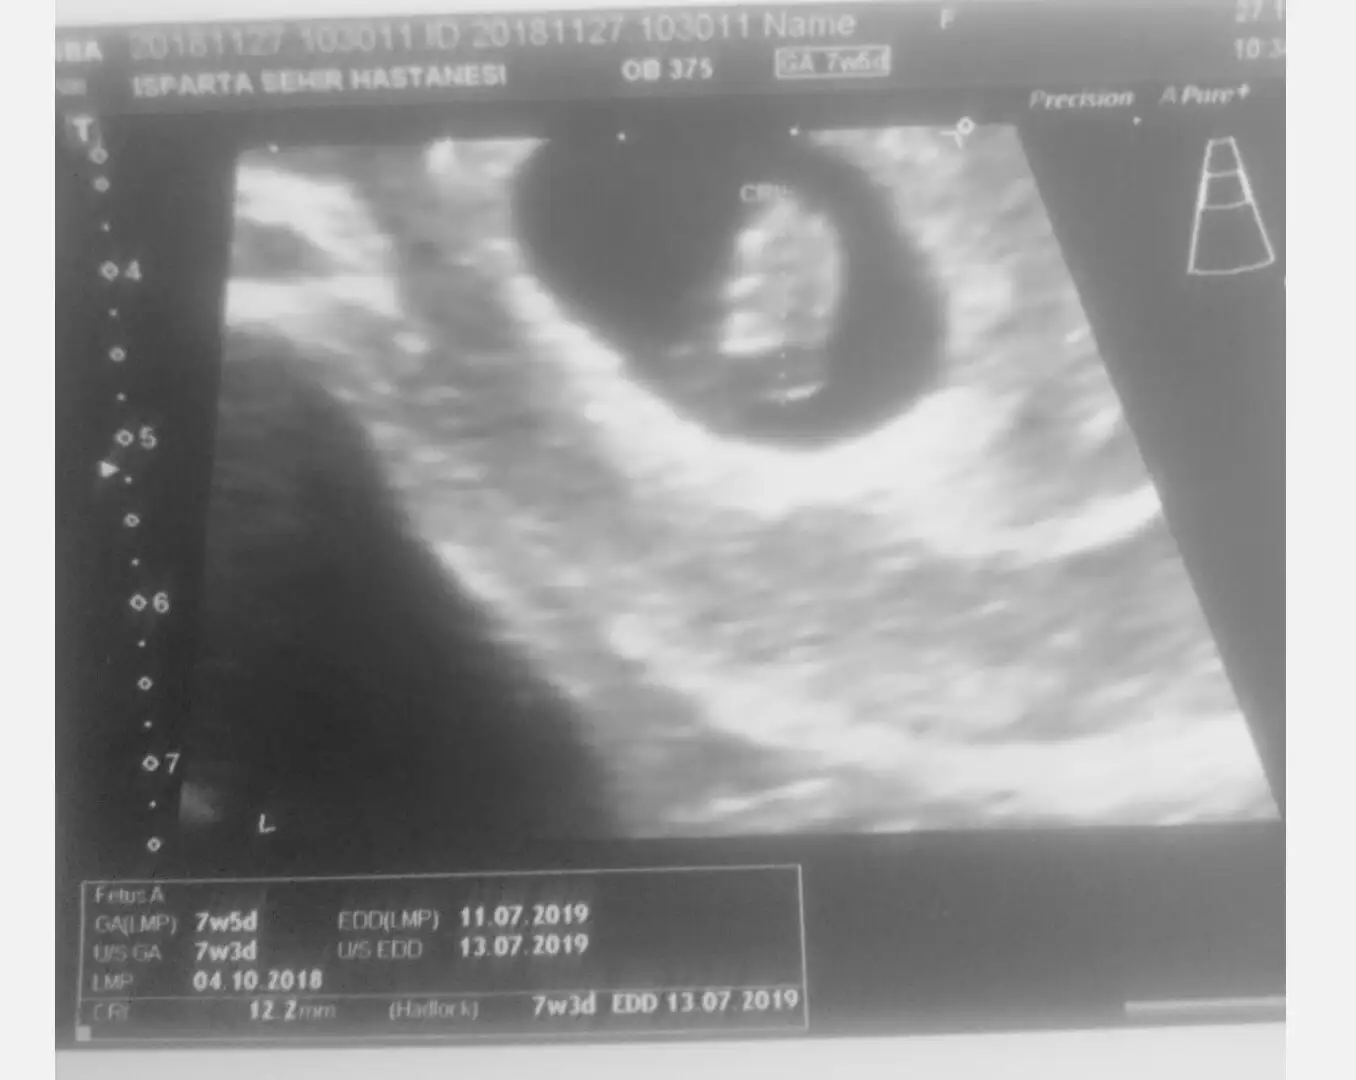

Üstteki ıkı kesenin görünümü bir tanesi boş. Boş olanı ölmedi. Burdada içinde bebek olanın ölçüleri.

Anam yavruma bak ben buradayım anne demiş. Kese boyları arasında fark pek yok ama karından daha geç görülebiliyor. Bekleyelim. Mevlam neylerse güzel eyler hayırlısı

Aynen canım Mevlam neylerse. Kese boyları ulytasomda daha net ve direk aynı ama içi boş görünüyor. Bebeğim sağlıklı olsun başka birşey istemiyorum şuanda. Yatın kontrole gideceğim sabırsızlıkla bekliyorum.

Teşekkür ederim. İki kese mevcut ikiz olacak dedi dr 15 gün önce. Ama şuanda kesenlerden birinde bebek var diğerinde bebek yok. Boş görünüyor. Yarın tek tekrar kontrole gideceğim. İnşallah ikiside bana tutunmuş olur. Dr ümitlenme boş kese olan düşecek dedi. İkiz olmasın zaten komplikasyonu çok fazla dedi.